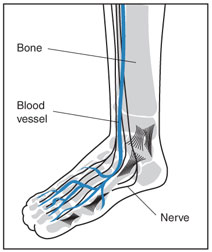

Diabetic peripheral neuropathy is a condition in which the nerves of the arms, hands, legs and feet become damaged by diabetes. Peripheral neuropathy can lead to numbness, loss of sensation, and sometimes pain. It is the most frequent complication of diabetes, eventually impacting 60% to 70% of persons with the disease.

Diabetes also causes inflammation of the blood vessel walls and atherosclerosis, or hardening of the arteries, leading to poor blood circulation in the lower extremities and development of peripheral artery disease (PAD). The lack of blood flow and constricted arteries also impair the body's ability to fight infection. Between 20-30% of people with diabetes also have PAD.